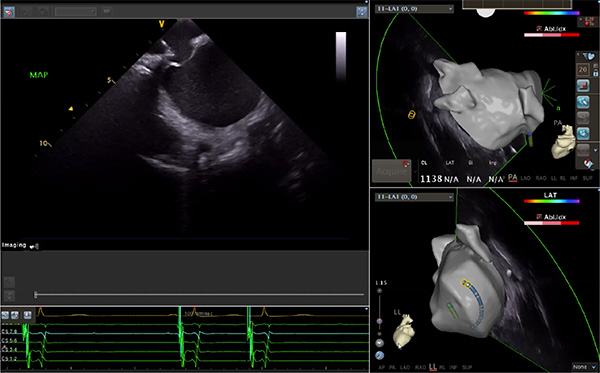

超聲心動(dòng)圖技術(shù)包括常規(guī)經(jīng)胸超聲(TTE)、經(jīng)食管超聲(TEE)、心腔內(nèi)超聲(ICE)、超聲聲學(xué)造影(MCE)、三維超聲心動(dòng)圖等,ICE是一種新興技術(shù)——將微型的換能器安裝在心導(dǎo)管的尖端,經(jīng)由外周血管輸送至心腔內(nèi)部,換能器發(fā)射聲波,對(duì)心臟及其鄰近組織進(jìn)行實(shí)時(shí)高質(zhì)量成像和(或)血流動(dòng)力學(xué)測(cè)定的超聲成像技術(shù)?;诓煌募夹g(shù)原理,心腔內(nèi)超聲導(dǎo)管被分為兩類:機(jī)械旋轉(zhuǎn)式超聲導(dǎo)管和相控陣超聲導(dǎo)管。目前,臨床上主要應(yīng)用的是相控陣超聲導(dǎo)管,ICE成像通過術(shù)者旋轉(zhuǎn)導(dǎo)管及操縱導(dǎo)管手柄上的兩個(gè)旋鈕來完成。

隨著心腔內(nèi)超聲的應(yīng)用更廣,性能也在逐漸優(yōu)化,已從二維成像轉(zhuǎn)變?yōu)?strong>三維成像,極大增強(qiáng)了引導(dǎo)及可視化能力。二維心腔內(nèi)超聲支持雙平面或三平面成像,可顯示兩個(gè)或三個(gè)不同的平面視圖,但醫(yī)生需將這些圖像在腦海中重新構(gòu)建為三維解剖結(jié)構(gòu)。三維心腔內(nèi)超聲則可直接呈現(xiàn)三維解剖結(jié)構(gòu)圖,便于醫(yī)生更輕松地開展手術(shù)。按照產(chǎn)品發(fā)展方向,預(yù)計(jì)心腔內(nèi)超聲還將向更清晰、精準(zhǔn)、多功能等方向發(fā)展。